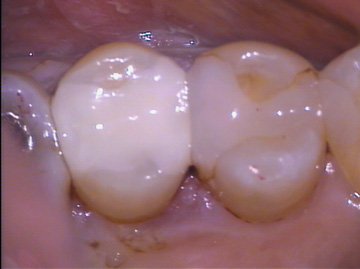

Porcelain filing and Composite Resin filling (both 3 years old)